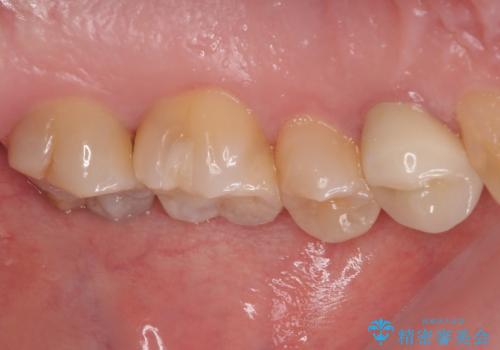

- 奥歯に物が挟まるとのことで来院された患者様です。

レントゲン写真より、奥歯2本に大きなむし歯があることが分かりました。

手前の歯はセラミックインレーで、奥の歯はオールセラミッククラウンにて治療を行うこととしました。

むし歯の範囲は大きかったですが、事前の症状もなく、処置後も一切の痛みなく快適に過ごすことができています。